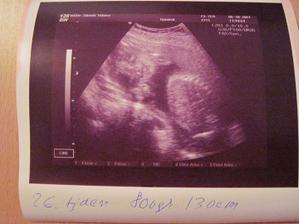

5.10.2011 kontrola 25+2, Emicka v poradku, 800g, 30cm bez nozek, asi budeme mit trosku delsi miminko:D